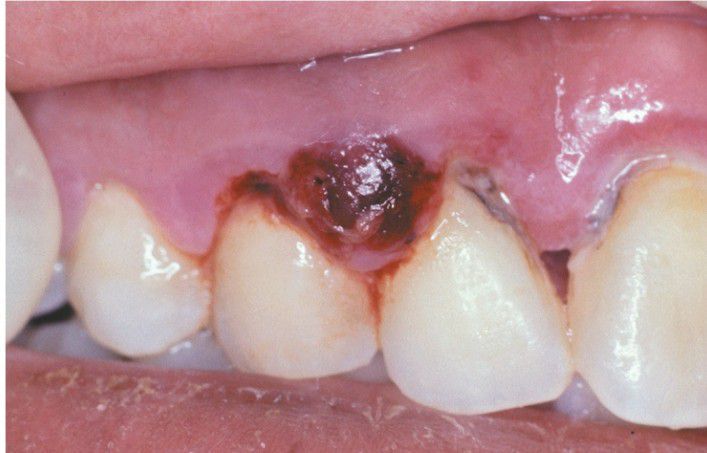

Periodontal Abscess

. Dark-red and hemorrhagic enlargement of the interdental papilla between the maxillary right lateral incisor and cuspid.